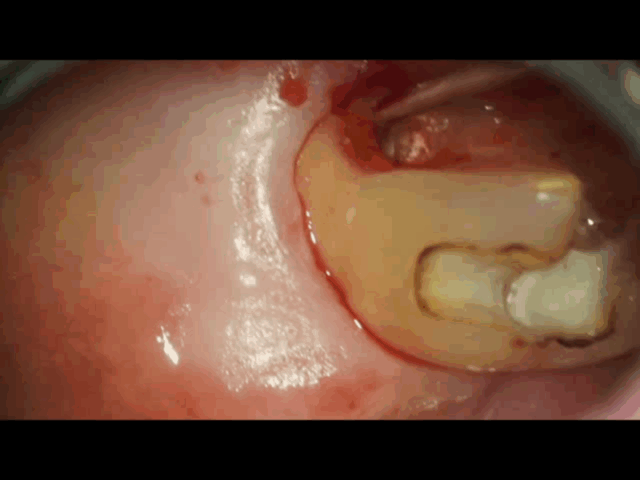

虫歯を完全に除去したら、神経の穴が露出しているので歯髄温存療法をします。 -

神経の穴からドバドバと出血があり、最初に5分程止血をします。

止血できたら正常な神経と判断でき歯髄温存をします。

すでに感染している神経は出血が治まらないです。止血ができないと歯髄温存は適応ではないとお話しております。

こちらはしっかりと止血ができているのでここから歯髄温存療法、MTAセメントを乗せていきます。 -

白い材料がMTAセメントです。

神経の穴に乗せて硬化させます。これで神経が露出してもMTAセメントで神経を温存することができます。

MTAセメントが硬化できたらCRで仮詰めをして歯髄温蔵療法の治療は完了します。